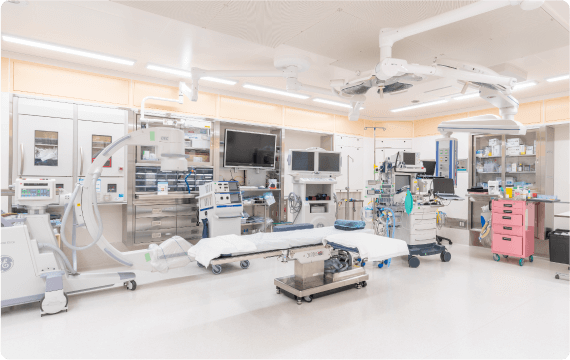

手術・麻酔

シムラ病院では増え続ける手術件数に対応できるよう、手術室を3部屋に増設しました。整形外科領域においては、広島大学四肢外傷講座と連携し、一般外傷から難易度の高い外傷手術まで幅広い整形外傷手術医療を提供しています。また、低侵襲で最先端の高度診療技術を活用した脊椎手術には自信があり、人工関節・スポーツ外傷に至るまで様々な分野における質の高い手術をお約束いたします。

シムラ病院では増え続ける手術件数に対応できるよう、手術室を3部屋に増設しました。整形外科領域においては、広島大学四肢外傷講座と連携し、一般外傷から難易度の高い外傷手術まで幅広い整形外傷手術医療を提供しています。また、低侵襲で最先端の高度診療技術を活用した脊椎手術には自信があり、人工関節・スポーツ外傷に至るまで様々な分野における質の高い手術をお約束いたします。

外科領域においては広島大学病院と連携し、呼吸器外科(肺)手術、乳腺手術、一般外科手術も行っており、多くの患者さまに喜んでいただいています。